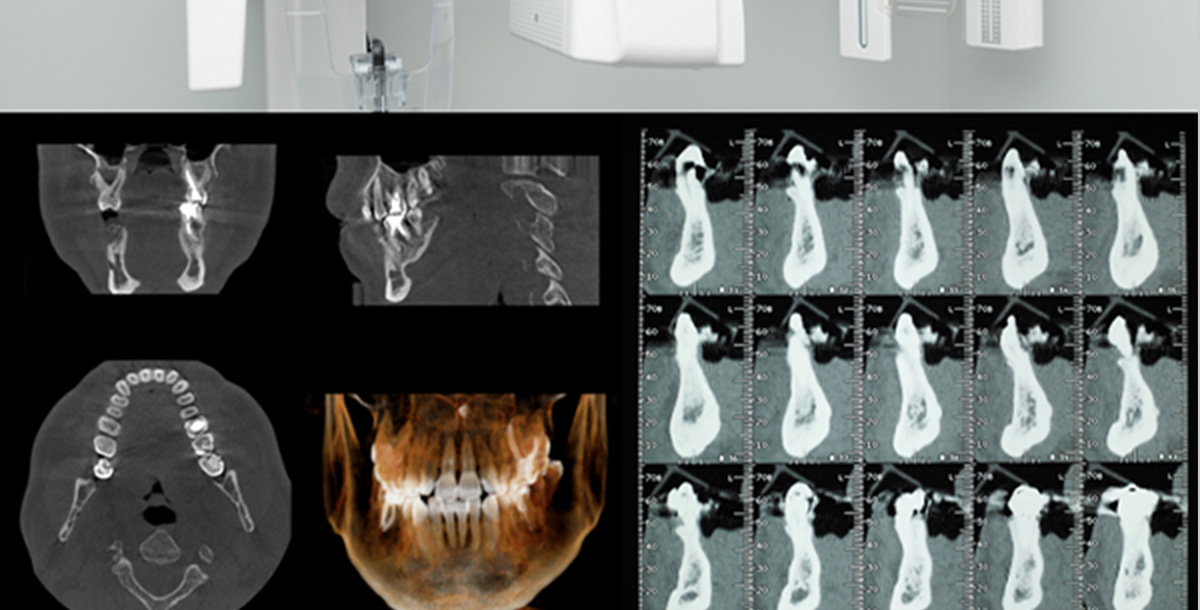

様々な症例ケースにも対応できるようインプラント専用の機器を導入し、インプラント埋入本数が1本から、上顎、下顎すべて(12本から)、骨造成術が必要な症例など、多様な患者様のインプラント治療に対応できる万全な体制で日々施術を行なっております。

顎の骨に人工物を埋め込んで行う施術のため、どの位置に神経や血管があるのか、骨の厚さが本当にインプラントに耐えうる厚みを持っているかなどを確認する必要があります。